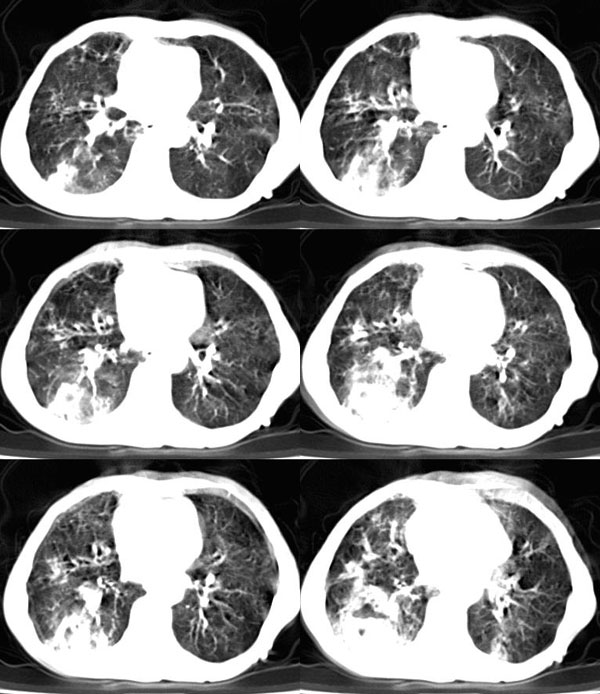

女:73岁;因一月前感冒后咳嗽,发烧,有大量脓痰,并且有恶臭味。

肺窗

补充_____伴双肺血行播散

谢谢辜兄为我们网站的兴旺所做出的杰出贡献!右下肺脓肿并双肺感染、右胸膜粘连。[emb21][emb20]

右下肺脓肿,两下叶,中叶支扩并感染,右侧胸膜肥厚粘连。

谢谢辜兄为我们网站的兴旺所做出的杰出贡献!右下肺脓肿并双肺感染、支扩,右胸膜粘连。